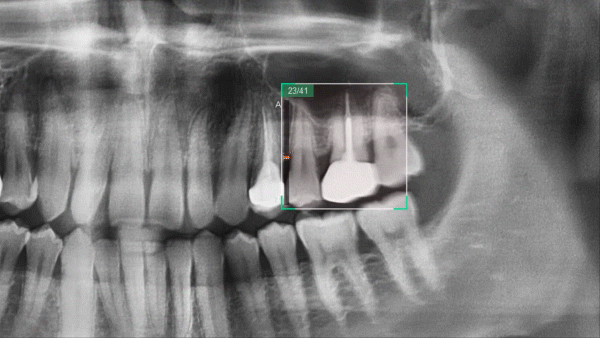

Новый шаг в развитии панорамной визуализации с Insight pan

Компьютерный томограф Green 16 от Vatech может снимать многослойное панорамное изображение, называемое Insight Pan, которое обеспечивает визуализацию в глубину панорамы. Поскольку у каждого пациента форма зубных рядов и наклон зубов могут отличаться, традиционные панорамные изображения могут иногда пропускать важные детали, которые оказываются за пределами единственного фокального слоя. Функция Insight Pan служит для получения многослойных панорамных изображений, гарантирующих возможность наблюдать необходимую анатомию на нужной глубине.

• • Скрытые корни и каналы

• • Расположение пульпы и гуттаперчи

• • Перелом корня или сломанный файл

• Insight Navi

Insight Navi в программе EzDent-i — это специальная функция для аппарата Green 16. Она позволяет получить информацию о внутренних структурах послойно перемещаясь на панорамном снимке вперед-назад.